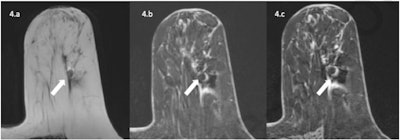

Overall, the Swiss authors report that magnetic markers are widely visible on MRI images due to the susceptibility artifact that they generate.

"However, the same artifact that accounts for visibility of the marker can possibly mask or mimic, depending on the circumstances, a residual tumoral enhancement and thus reduce the diagnostic accuracy of MRI," they wrote. "Indeed, the size and appearance of metallic artifact on MRI depends on several factors, namely the material of the clip (in particular its magnetic susceptibility), the magnetic field strength of the system, and the sequence itself (gradient echo or spin echo are not equally sensitive to the presence of metal)."